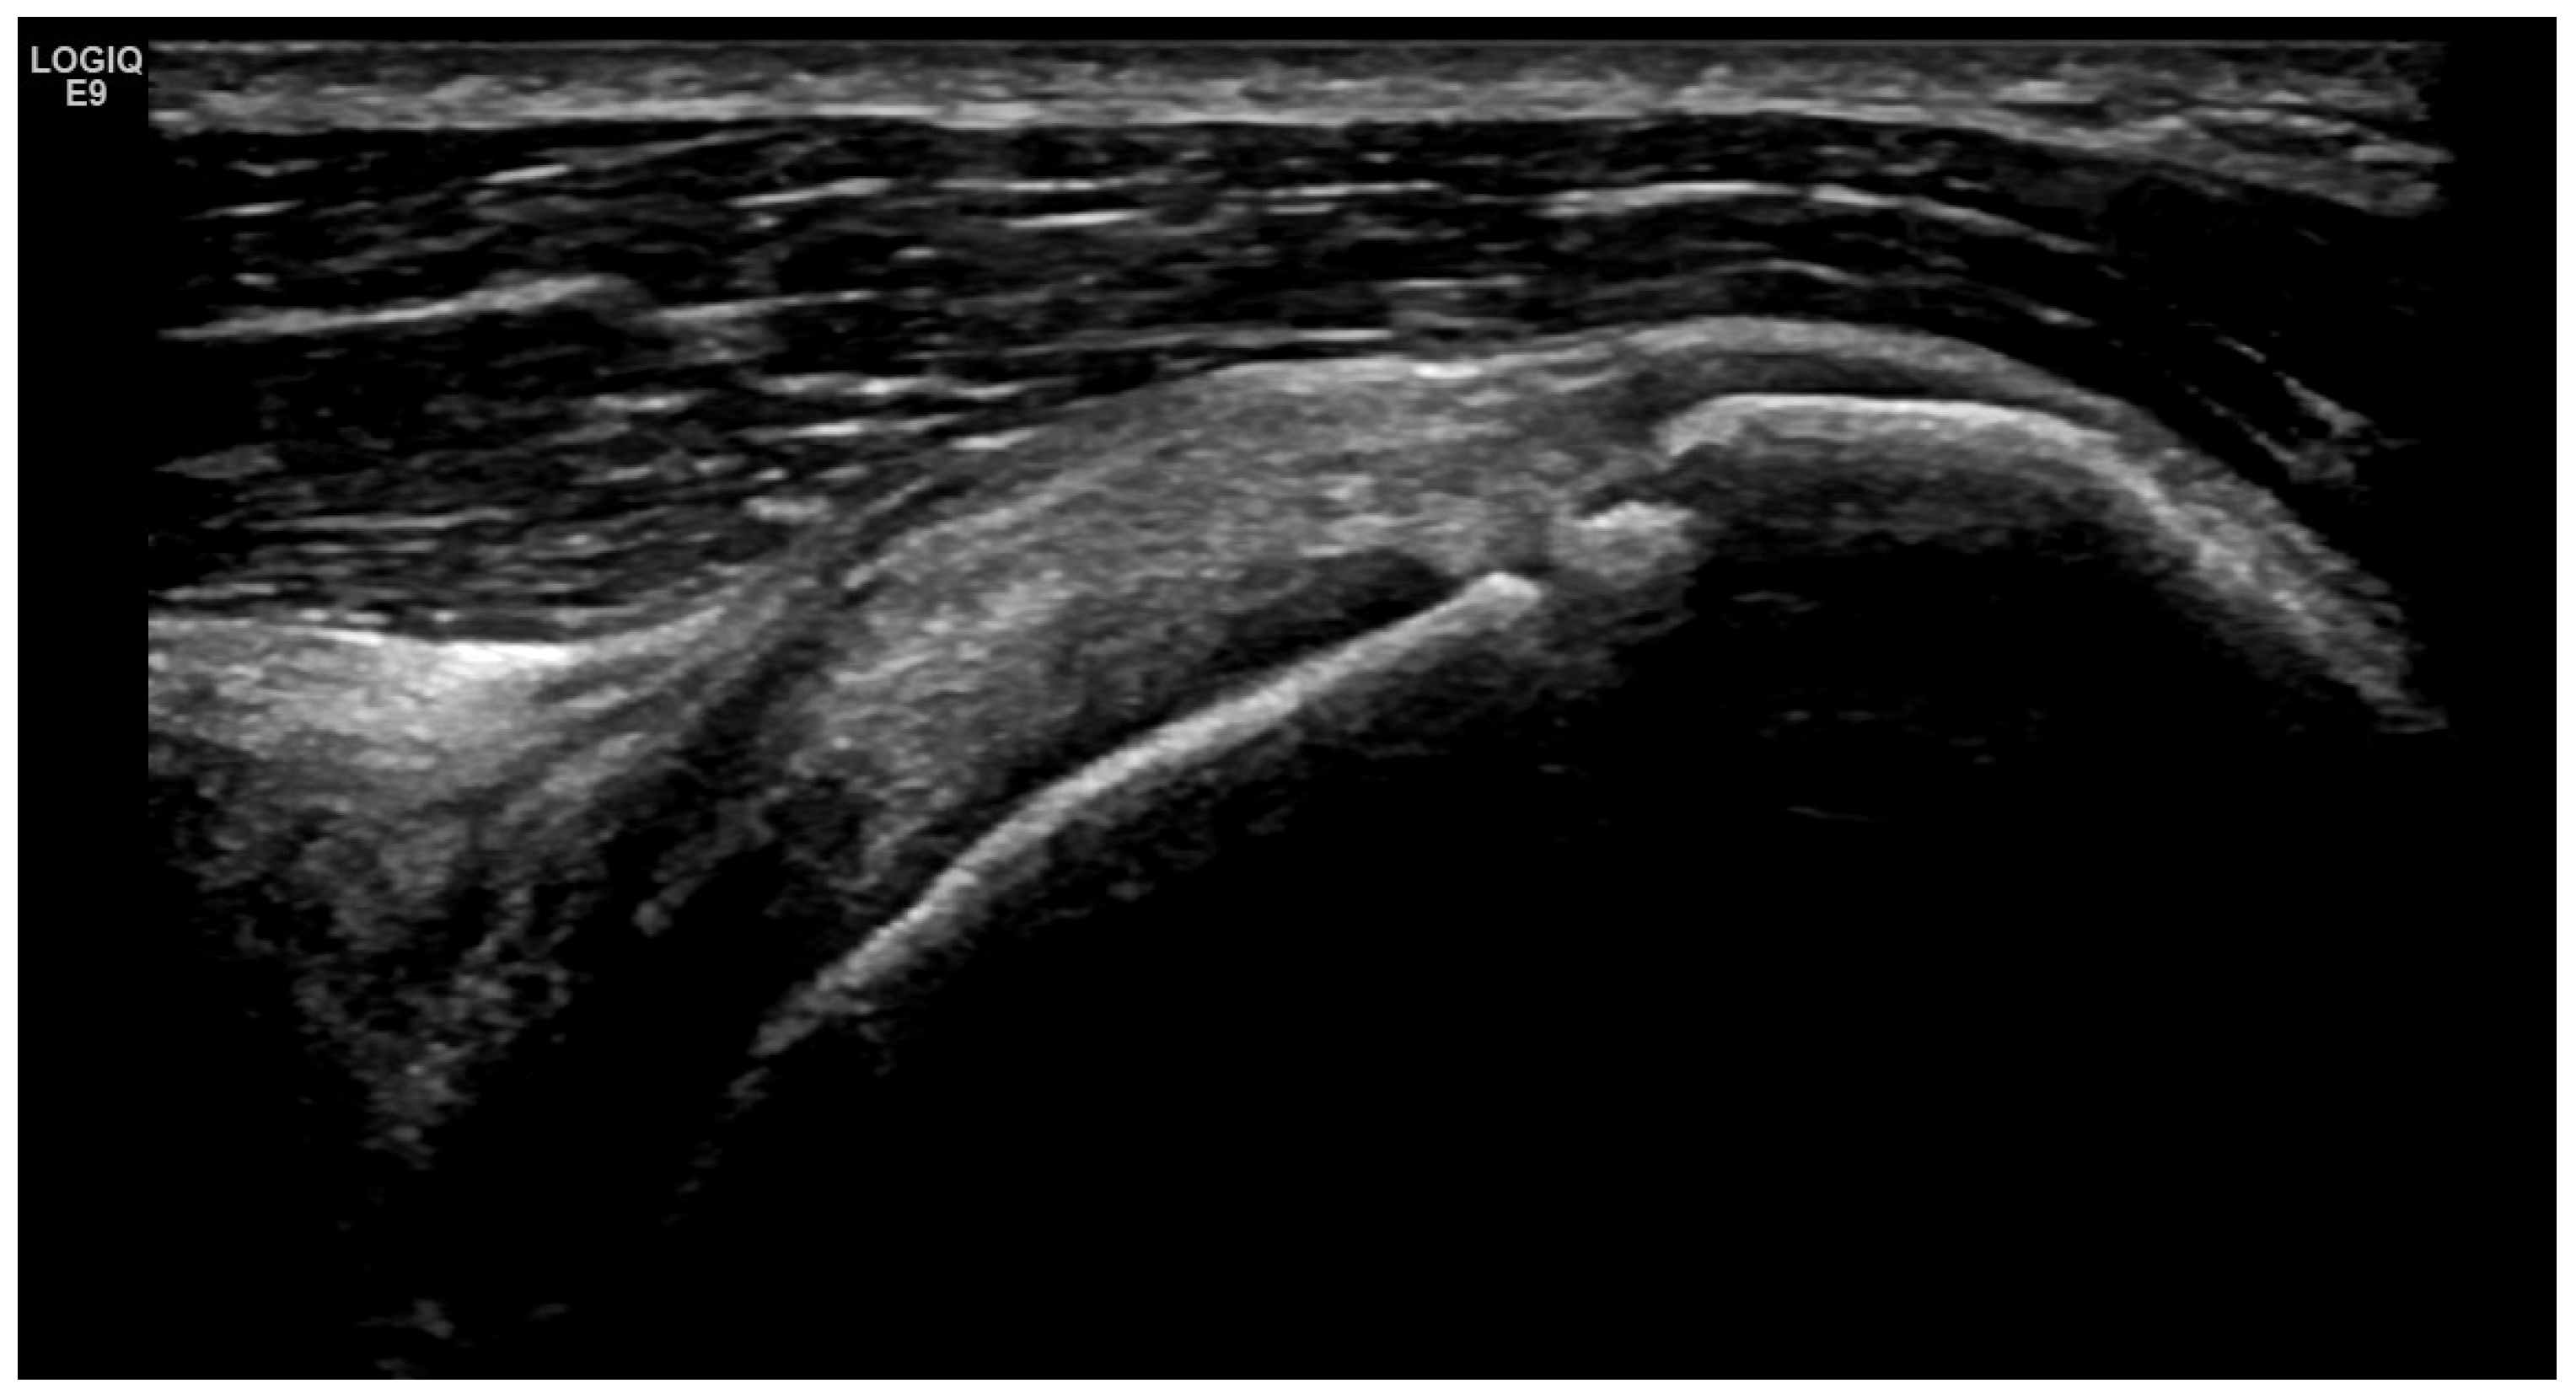

4. Examples of US Phenotypes